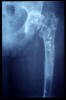

Fractura intertrocantérea de fémur, osteosíntesis

Fractura de fémur, osteosíntesis

osteosíntesis fractura fémur